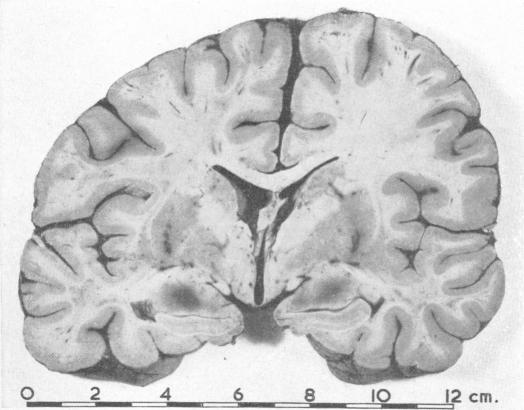

Association of brain damage with therapeutic abortion induced by amniotic-fluid replacement: report of two cases.

Br Med J. 1966 Apr 23;1(5494):1010-3. doi: 10.1136/bmj.1.5494.1010.